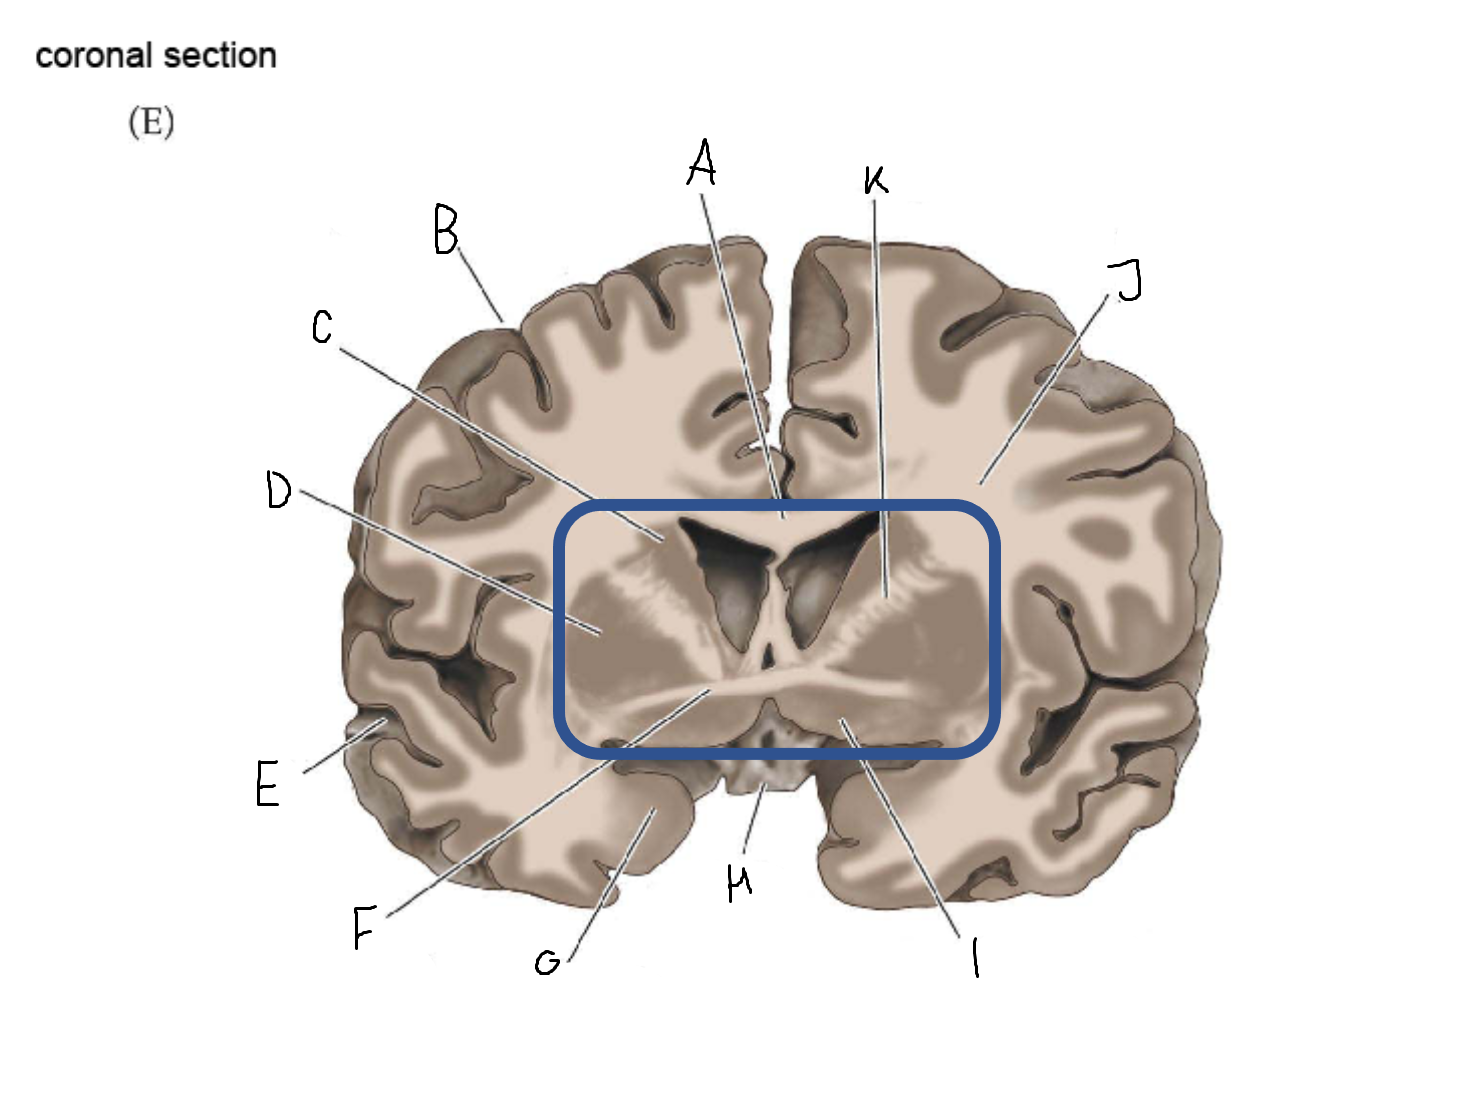

A

head of caudate nucleus

C

putamen

D

external segment of globus pallidus

E

internal segment of globus pallidus

F

third ventricle

G

thalamus

A

corpus callosum

B

cerebral cortex

C

caudate

D

putamen

F

anterior commissure

G

amygdala

H

optic chiasm

I

basal forebrain nuclei

K

internal capsule